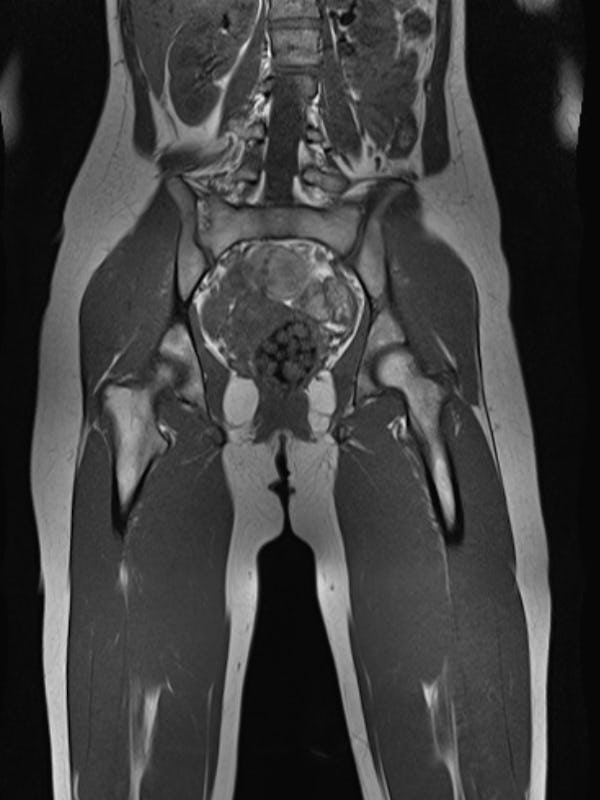

The best part were the images.

My whole body, bisected and laid bare for inspection.

Example scans, courtesy of Prenuvo.